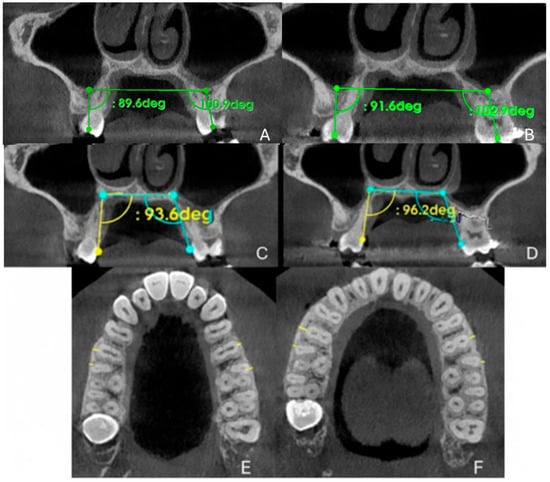

| Measurements | Pre-Treatment | Post-Treatment |

|---|---|---|

| PMW (mm) | 28.04 | 34.5 |

| IMW (mm) | 36.08 | 50.02 |

| SE (mm) | 0.32 | 7.82 |

| M16 (mm) | 0.6 | 0.7 |

| M15 (mm) | 1.6 | 2.3 |

| M25 (mm) | 0.7 | 1.3 |

| M26 (mm) | 1.2 | 0.9 |

| PAA 16 (°) | 93.6 | 96.2 |

| PAA 26 (°) | 109.6 | 112.2 |

| DTA 16 (°) | 89.06 | 91.6 |

| DTA 26 (°) | 100.9 | 102.9 |

2.9.3. Evaluation of Dental Effects: Alveolar Bending, Palatal Alveolar Angle, Dental Tipping and Bone Dehiscence

3.4. Evaluation of Dental Effects: Palatal Alveolar Angle, Buccal Tipping Angle, Bone Dehiscences and Fenestrations